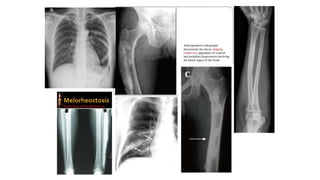

Melorheostosis:

⮚ Melorheostosis can be both a sporadic, non-inherited disorder or an

inherited disorder presenting with melorheostosis and osteopoikilosis.

⮚ Melorheostosis is a benign condition characterised clinically by pain and

soft-tissue contractures.

⮚ Other bones like skull, ribs, spine and short tubular bones can be affected at

times.

⮚ There is typically cortical thickening in a streaky or wavy pattern extending

from the proximal to distal part of bone giving a “flowing wax candle

appearance”.